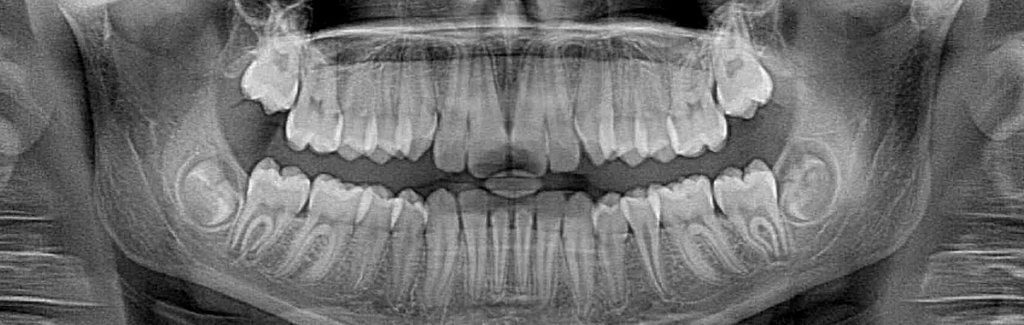

Dental X-rays enable dentists to see decay inside teeth that would not be visible to the naked eye. This allows us to act earlier against cavities, which is much better for the teeth. However, X-rays do expose patients to radiation, which is why you always wear a lead apron when the images are being taken. Thanks to advances in technology, there is now a safer way to take these images.

Film X-rays have been used in dentistry for decades. In the past few years, many forward-thinking dentists like Dr. Blackman have invested in digital X-ray technology. Film X-rays cost a bit less than digital X-rays but the increased exposure to film X-rays is more harmful to a patient’s overall health. Our digital X-ray emits as much as 85 percent less radiation than traditional X-ray technology.

Digital X-rays are one of the most important new advances in our office. We are not only able to reduce your exposure to radiation but also increase the diagnostic proficiency. In addition to increased diagnostics, we reduce the amount of harmful chemicals and other waste materials associated with traditional X-ray technology. The reduction in waste was a big consideration when deciding to invest in digital technology. We pride ourselves in being environmentally responsible.